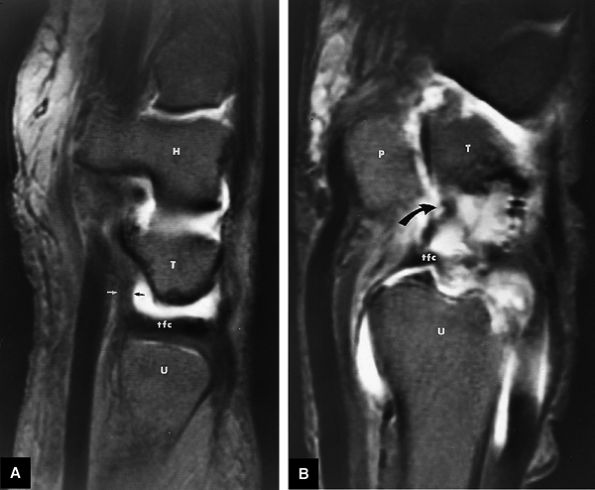

FIGURE 10.2 ● Optimized signal-to-noise in routine wrist imaging using a four-channel phased-array wrist coil on a 3T imager. (A) Coronal PD FSE image. (B) Coronal FS PD FSE image. (C) Axial PD FSE image.